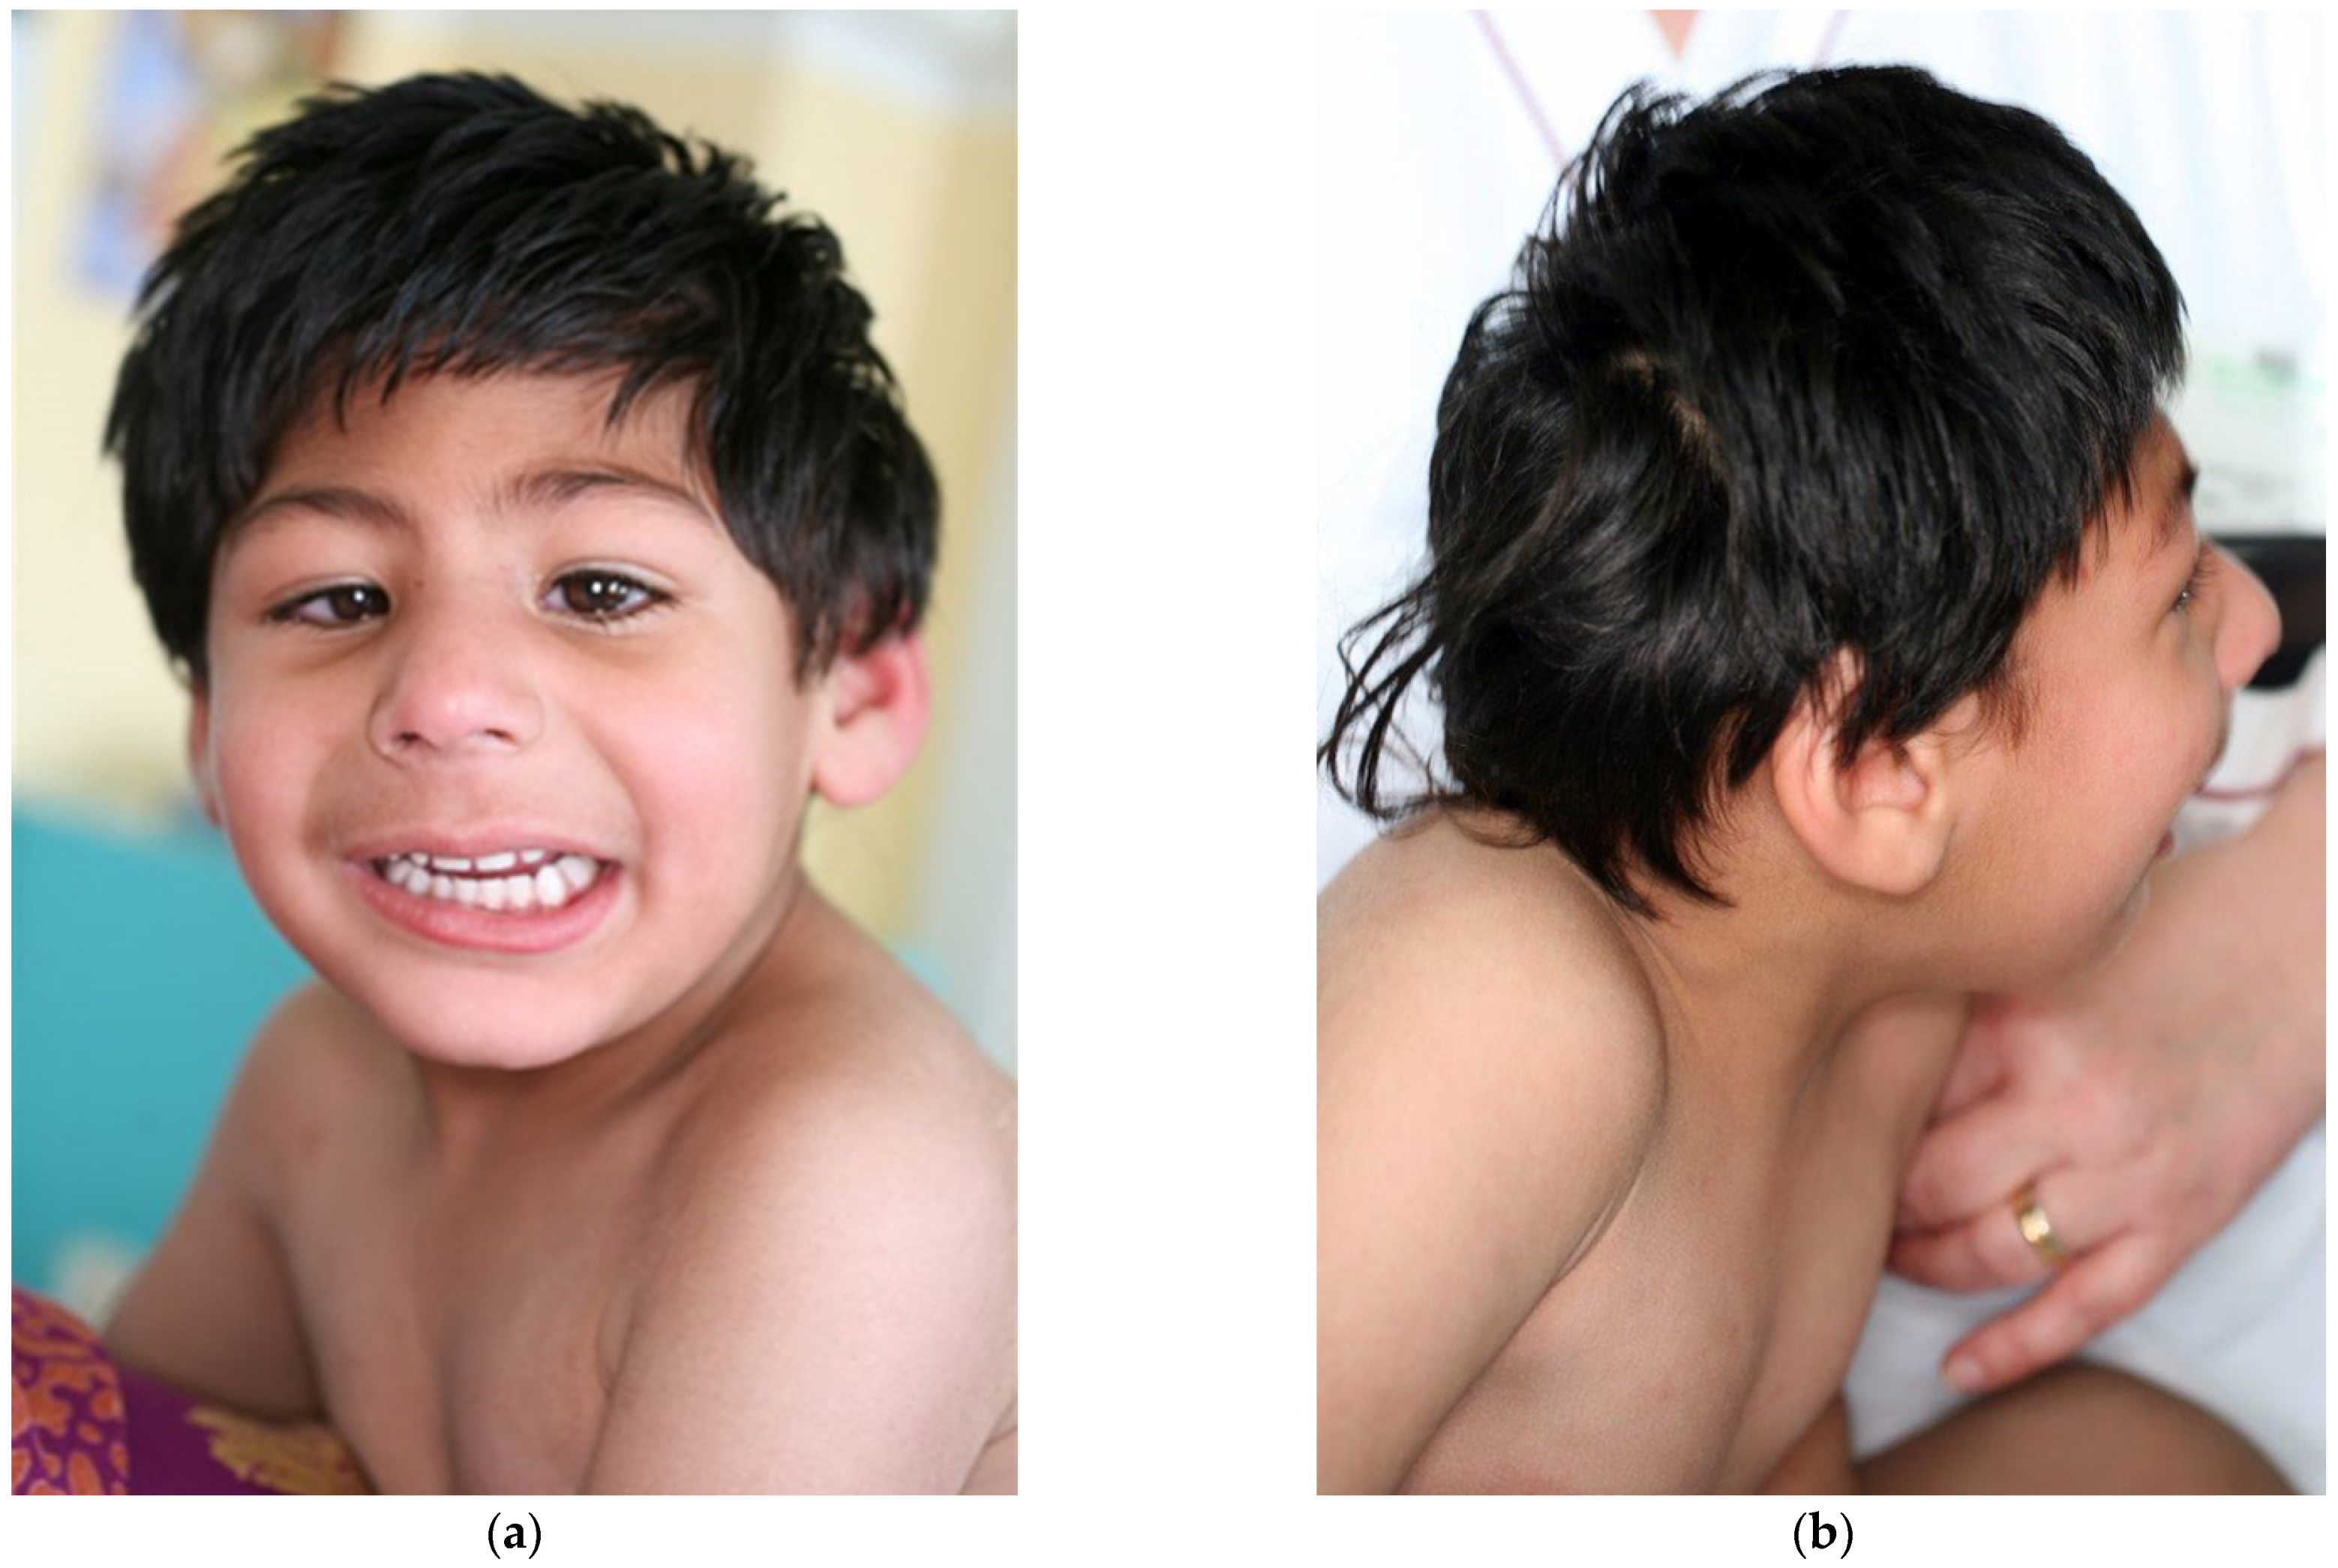

| This report | 1 | del ex 1−8 | −3.5 | −5 (10 y) | −2 | mild DD, profound ID (no language) | fronto-polar simplified gyral pattern, PNH, mild ventriculomegaly, enlarged posterior fossa | sloping forehead, highly arched eyebrow, exotropia, epicanthus, large ears; hyperactivity | Pakistani (northeast) |